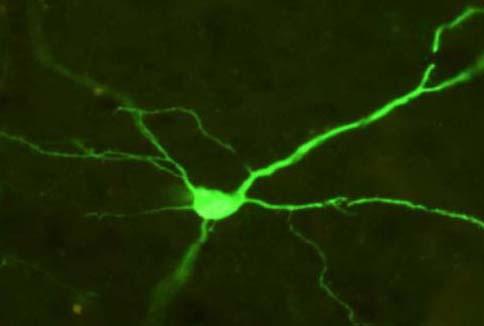

To test the causal imbalance, Heidi C. Meyer, a graduate student working in Professor David J. Bucci's Neurobiology of Learning and Memory Laboratory at Dartmouth, used a chemogenetic approach, known as Designer Receptors Exclusively Activated by Designer Drugs (DREADDs), to simulate the imbalance that takes place during adolescence by simultaneously altering the activity in PFC and NAC. DREADDs enables researchers to "remotely control" the activity of brain cells by temporarily turning cells off or on in a region for a short period of time, by injecting a virus that transfers genes for a synthetic receptor, which is only responsive to a synthetic drug that is also administered through a simple injection, which turns brain cells off or on temporarily.